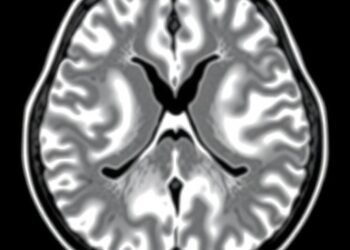

In a groundbreaking advancement poised to revolutionize hepatocellular carcinoma (HCC) treatment, researchers have unveiled a novel MRI-based deep learning model ...